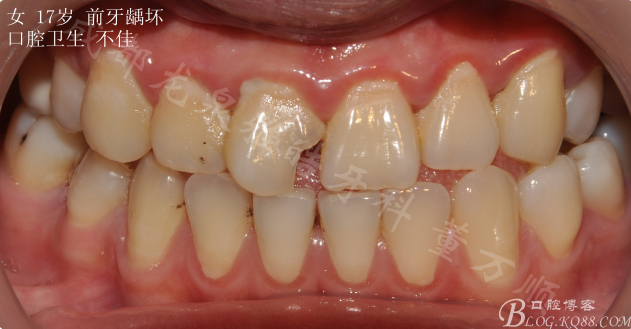

一個漂亮的女孩 17歲

常規(guī)口內(nèi)檢查可見 口腔衛(wèi)生差 前牙齲壞 自述早上冷水刷牙會有不適(磨牙基本上都有齲壞)

主要先解決前牙美觀問題 12 21鄰面均有齲壞